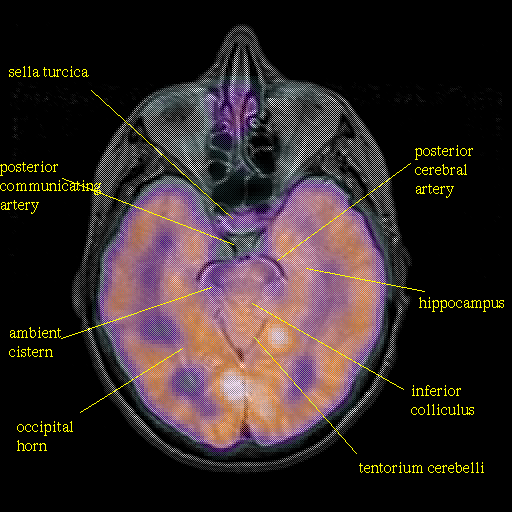

overlay : Slice 21

Slice 21